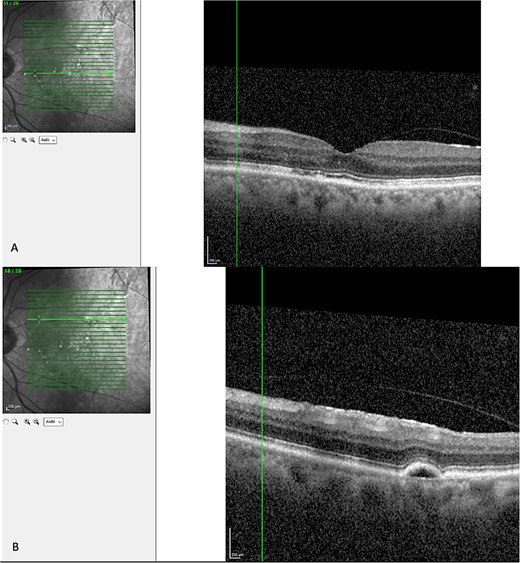

Finally, the patient was seen 12 months later. His left eye vision was 6/9 and his OCT showed a serous PED, with resolution of subretinal or intraretinal fluid as seen in Fig. 5.

Latest OCT of the patient’s macular. (A) Shows absence of intraretinal or subretinal fluid. (B) Shows a pigmental epithelial detachment.